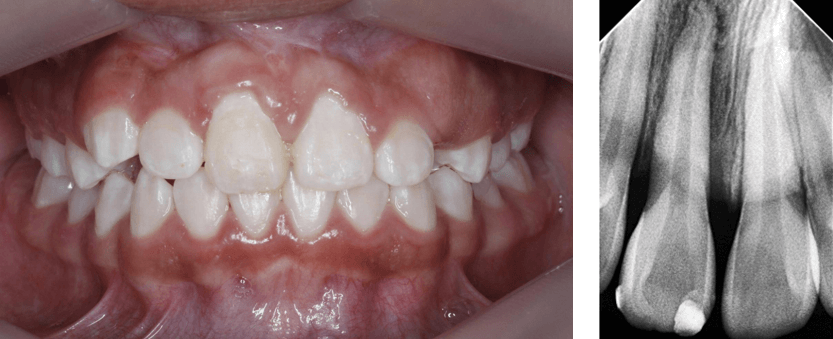

Una vez finalizado el proceso de tracción y alineación del incisivo 1.1, se retiró la aparatología fija empleada para la técnica (Fig. 27), se evaluó la vitalidad pulpar con cloruro de etilo en spray, dando una reacción positiva. Para el control radiológico se tomó la Rx periapical (Fig. 28) con el propósito de verificar el estado del hueso circundante en el ápice. Nótese en dicha radiografía un halo radiolúcido circundante a la raíz del incisivo 1.1, propio del proceso de aposición de hueso alveolar cercano a un diente traccionado.

Fig 27. Fotografía post retiro de aparatología fija - Fig 28. Rx periapical N4

Fig 27. Fotografía post retiro de aparatología fija

Fig 28. Rx periapical N4

Resultados

Después del retiro de ortodoncia interceptiva para realizar la tracción del IC 1.1, se realizó un control a los 6 meses para verificar los resultados del tratamiento. En esta cita se hizo una prueba de sensibilidad pulpar con cloruro de etilo con respuesta positiva, una radiografía periapical de control (Fig 29) así como la fotografía intraoral de frente (Fig 30) y un escaneo digital (Fig 31 y 32 ). En la radiografía periapical se observa ya un proceso de formación de hueso alveolar alrededor de la raíz del diente traccionado, incluida la formación de lámina dura como cortical alveolar.

Fig 29. Rx periapical N5 - Fig 30. Fotografía de control 6 meses después de retiro

Fig 29. Rx periapical N5

Fig 30. Fotografía de control 6 meses después de retiro